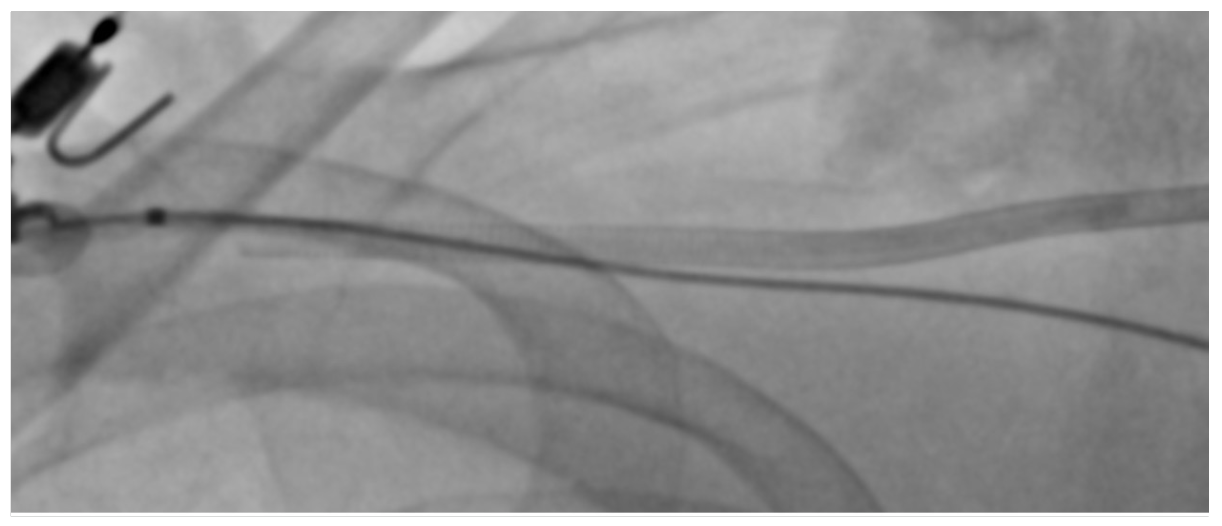

We then tried a 6 Fr Angio-Seal device (Terumo), but were unable to pass the inner part of the device with the collagen plug into the soft outer sheath which was kinked again at the indicated site (Figure 3). However, when we were retrieving the Angio-Seal, the foot plate was inadvertently trapped in the top part of the outer sheath. We maintained access after bypassing the caught foot plate with a needle introducer and wiring of the kinked outer sheath with an 0.018-inch Glidewire Advantage (Terumo) (Figure 4).